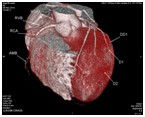

心脏大血管CT成像